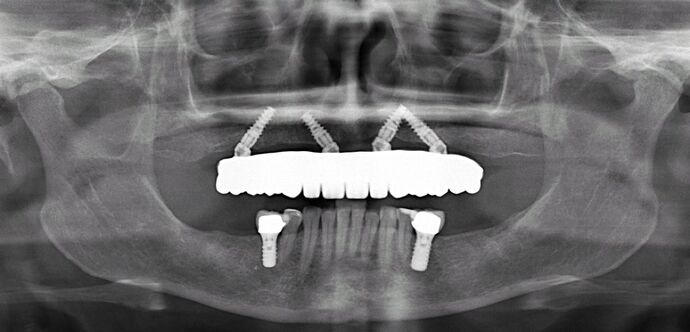

This patient had spent her whole life at the dentist’s office and had spent thousands of dollars on fillings, crowns, root canals, bridges, remake of bridges all of which eventually were failing and she was referred to Dr Bidra for comprehensive permanent solutions. Dr. Bidra determined that most of her lower teeth could be saved but her upper teeth needed a permanent All on 4 bridge which was all accomplished in 1 day without any bone grafting! The bottom jaw received just 2 implants after removal of diseased teeth.

Procedures : extractions, implants, All on 4 , Teeth in a day, no bone grafting and full mouth reconstruction with monolithic zirconia bridges.